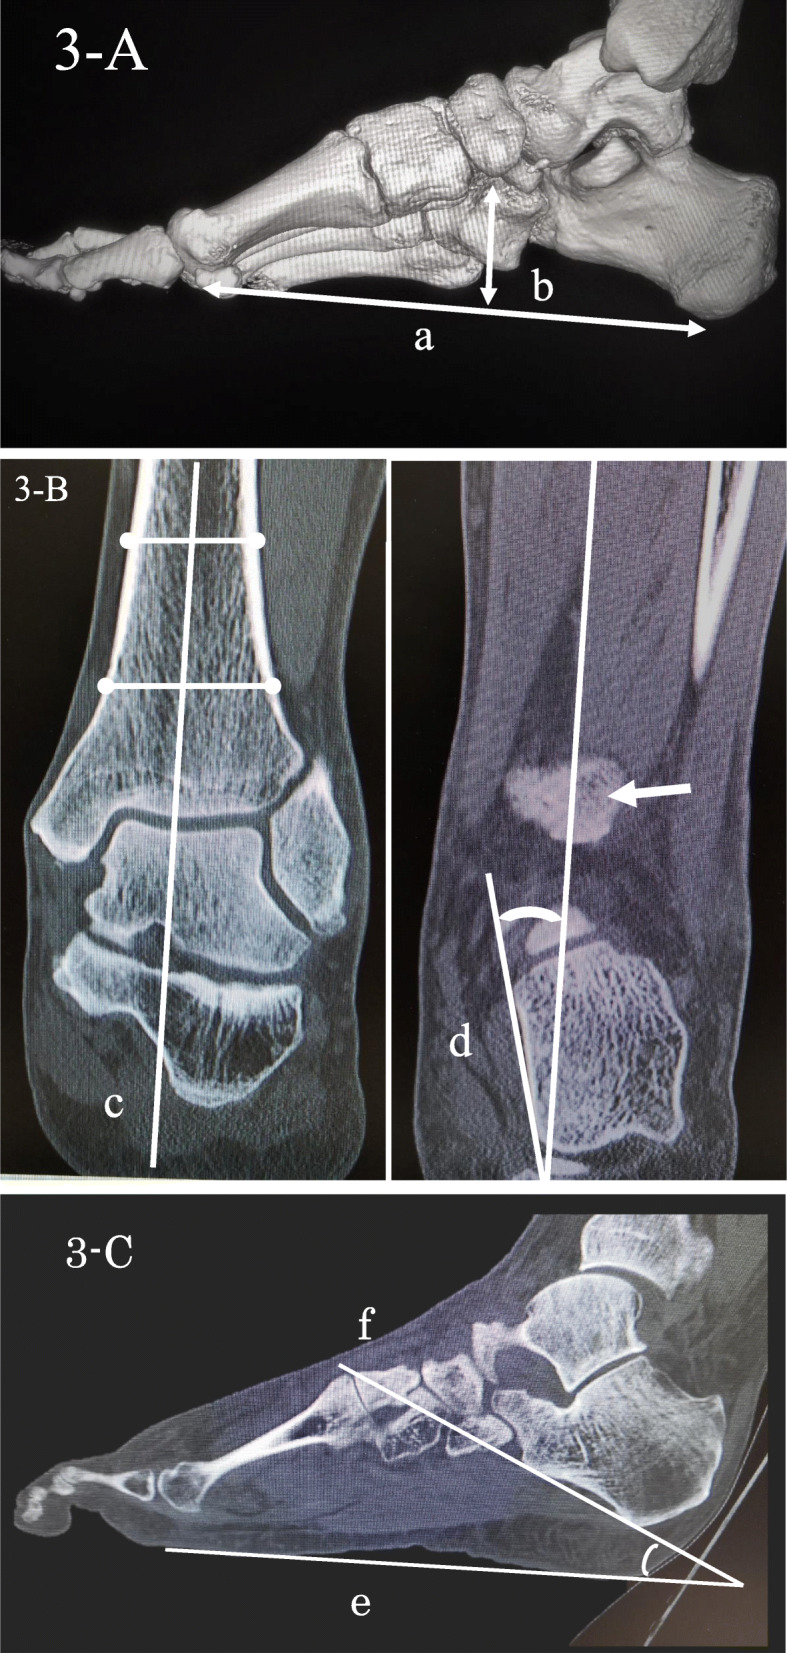

CT (Toshiba Aquilion, Canon Medical Systems Cooperation, Otawara, Japan) was performed with the standard bone CT protocol with 0.5-mm axial sections in three planes, with a tube voltage of 120 kV. After creating a 3D computed tomography image, three criteria were evaluated. First, the navicular index was evaluated according to a method described by Roth et al. [19]. They introduced the navicular index as a new measure to distinguish between flatfoot and normal foot. A greater navicular index suggested a higher likelihood of a flatfoot. A line connecting the lowest point of the first metatarsal head to the lowest point of the calcaneus was created with the 3D CT image. The distance between the lowest point of the first metatarsal head and the lowest point of the calcaneus was defined as “the length of the longitudinal arch.” A plane was subsequently created to passed through the lowest point of the first metatarsal head, the lowest part of the fifth metatarsal head, and the lowest part of the calcaneus. The distance of the perpendicular line from the lowest point of the navicular bone to this plane was measured and defined as “the navicular height” (Fig. 3A). The navicular index which was calculated by dividing the length of the longitudinal arch with navicular height was investigated. A higher navicular index indicated a lower arch height. Second, the tibiocalcaneal angle was evaluated according to a method described by Lee et al. [20]. This angle was defined as the angle between the axis of distal tibial shaft and the medial calcaneal contour. The axis of the distal tibial shaft was first drawn through the centre of the tibial shaft, which was defined by the midpoint of two pairs of points on the distal tibial cortex in coronal CT image through the maximum width of the tibial shaft. Then, a line of the medial calcaneal contour was drawn along the medial calcaneal wall in coronal CT image through the posterior tibial cortex. The resulting angle between these 2 lines was defined as the tibiocalcaneal angle (Fig. 3B). Third, the calcaneal inclination angle was evaluated according to a method described by de Cesar Netto et al. [21]. This angle was defined as the junction of 1) the plantar line and 2) a line connecting the most inferior point and edge of the calcaneal tuberosity and anterior process of the calcaneus in sagittal CT image, respectively (Fig. 3C). The latter two are both part of the assessment used to evaluate flat feet. Since these two radiographic angles are well correlated with weight-bearing and non-weight-bearing conditions [21, 22], the measurement can be carried out without concern for load conditions. SYNAPSE VINCENT Ver. 3.3 (FUJIFILM Cooperation, Tokyo, Japan) was used for these measurements as an image analysis software. CT images were evaluated independently by orthopaedic surgeons with 15 years of clinical experience and were blinded to the clinical and patient data.

Fig. 3.

The methodology of measuring the longitudinal arch length and navicular height with 3DCT imaging (A), tibiocalcaneal angle with coronal CT image (B), and calcaneal inclination angle with sagittal CT image (C). A. a: The length of the longitudinal arch. b: The navicular height. B. c: The axis of the distal tibia. d: A line of the medial calcaneal contour. White arrow: The posterior tibial cortex. C. e: The plantar line. f: The most inferior point of the calcaneal tuberosity and the inferior edge of the anterior process of the calcaneus